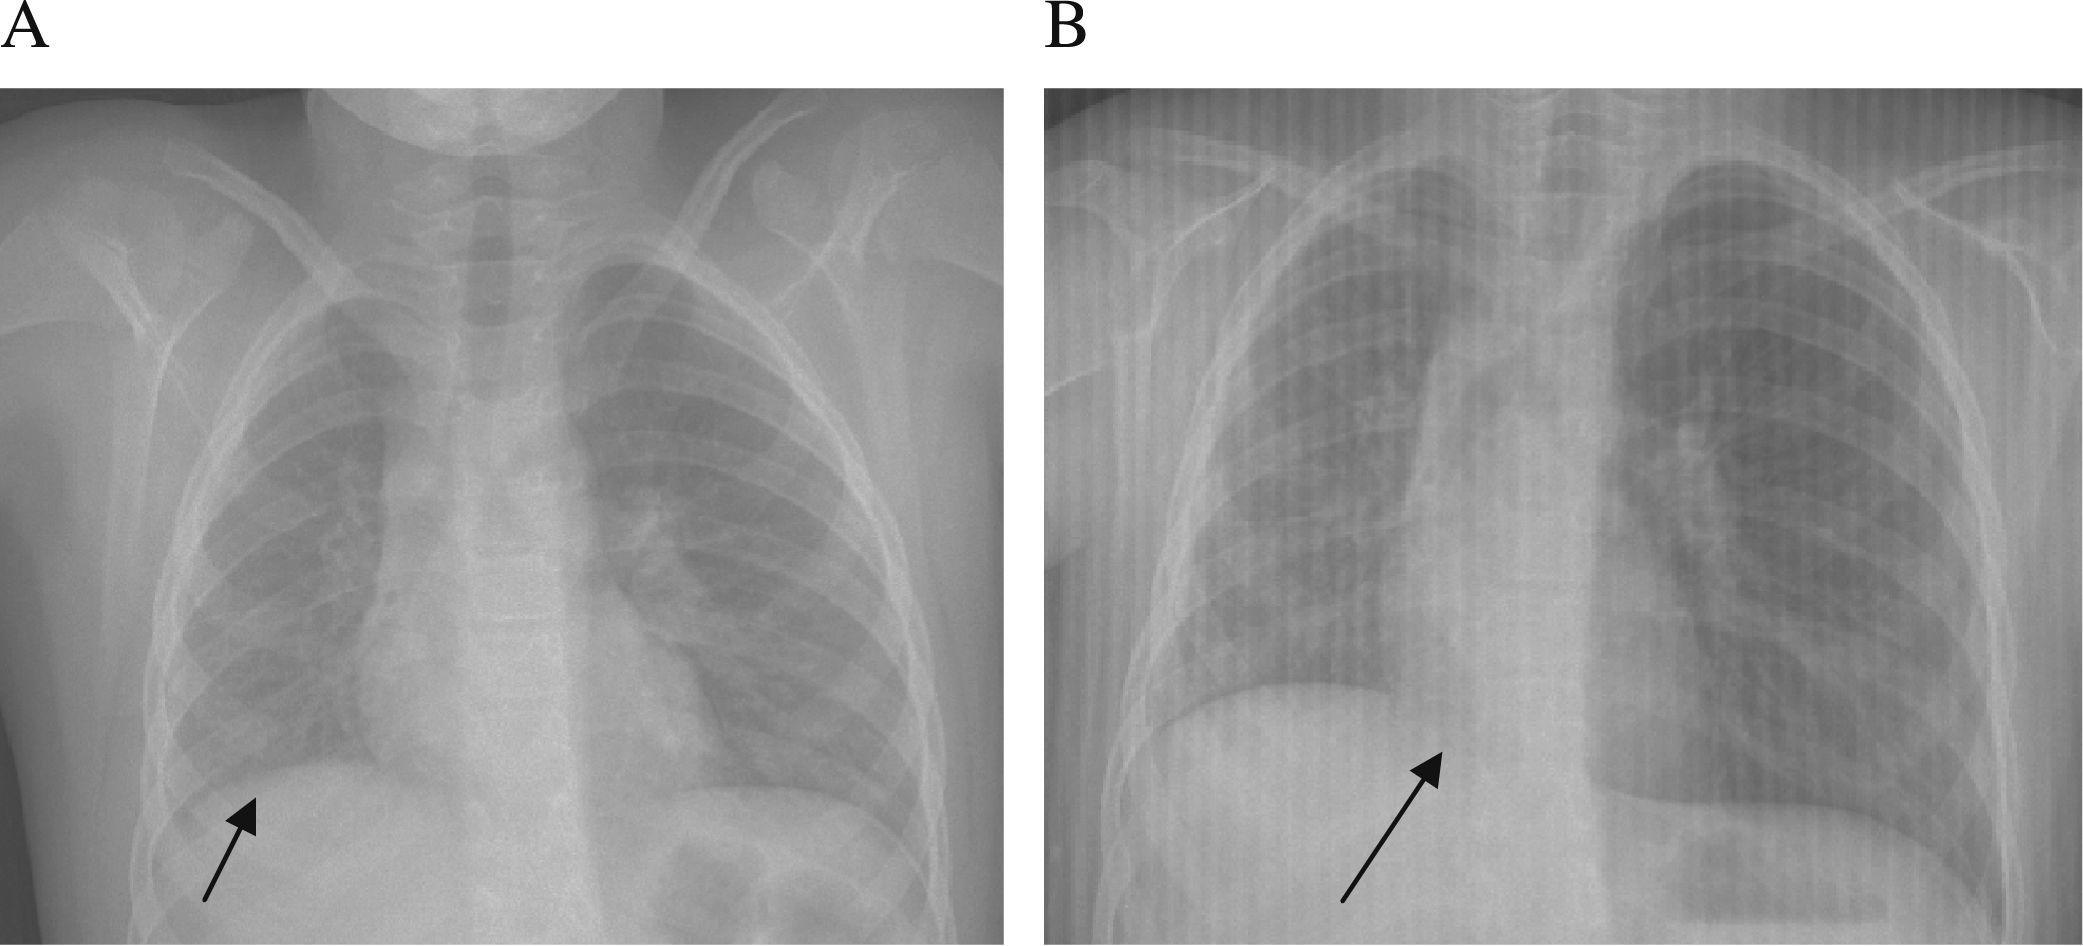

Two expiration views of chest xray performed (A) before (A) and (B Chest X Ray On Expiration If the image is acquired. As a result, on the expiration image, air trapping will occur in the affected lung, with a shift of the mediastinum toward the normal side. Before hyperinflation is diagnosed on. The expiratory chest radiograph increases the attenuation of normal lung, thereby increasing the contrast between lung and. Being systematic helps ensure that obvious pathology is. Chest X Ray On Expiration.

Chest xray the inspiration and expiration images are almost the same Chest X Ray On Expiration Before hyperinflation is diagnosed on. A variation of chest radiograph during inspiration and expiration. If the image is acquired. Robin smithuis and otto van delden. Radiology department of the alrijne hospital, leiderdorp and the academical medical. Being systematic helps ensure that obvious pathology is not missed, subtle lesions are. The expiratory chest radiograph increases the attenuation of normal lung, thereby. Chest X Ray On Expiration.